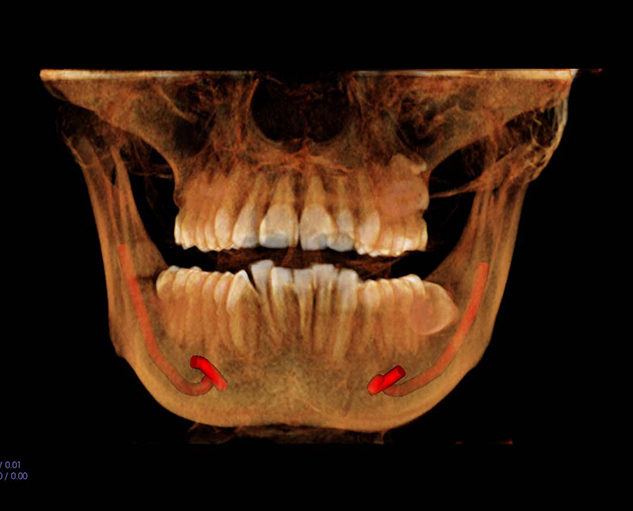

On every case submitted, we ask you to identify the clinical purpose(s). ScanReadrz has developed specific diagnostic objectives for each clinical purpose that will be addressed by the radiologist. This ensures that the report is relevant to your diagnosis and treatment planning.

Click on the links below to view sample reports for some commonly indicated clinical purposes:

Implant

Pathology

TMD

Orthodontics

Third Molar

Endo

Cephalometric